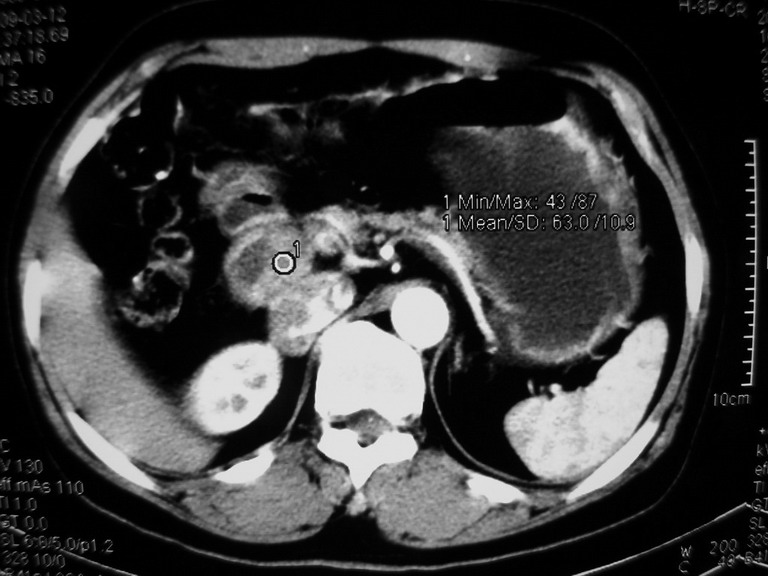

患者,女性50岁,上腹部不适2年余,既往多次腹部彩超未见异常,今日上午在我院查彩超发现肝右叶囊实性病变,外院辅助检查,afp,cea,ca199, 都在正常范围内,无肝炎史否认肿瘤史,生活在牧区

接着往下一贴看,有静脉期和延迟期,在看看和下腔静脉及十二指肠的关系,腔静脉内是不是栓子?

考虑肝右叶与尾叶交界区肝癌(部分外生),侵犯下腔静脉并下腔静脉瘤栓形成。

肝包虫病可能性大